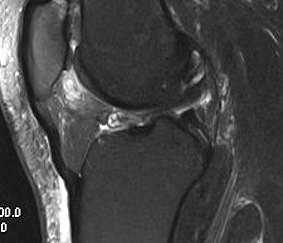

MRI

See increased signal in fat pad